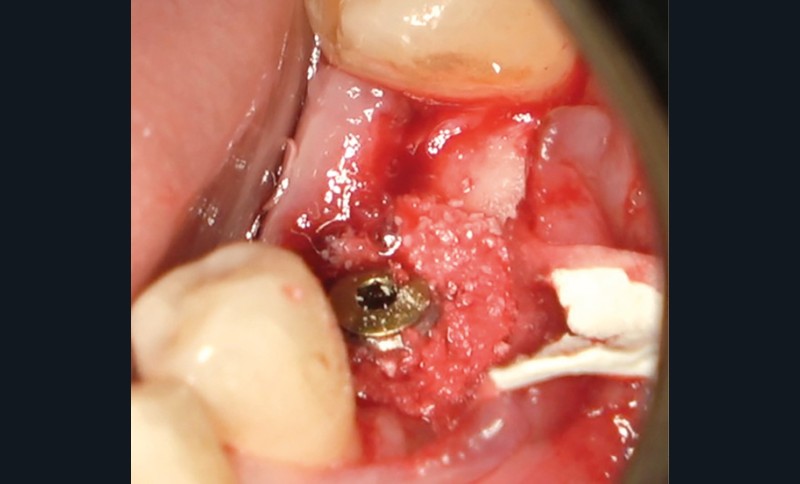

- Avulsion de la 36 et régénération osseuse guidée (ROG) réalisée en 2017 suite à une fracture de la dent et une infection

- Un implant posé en 2018 après la fin du traitement orthodontique

- Péri-implantite diagnostiquée en 2021

Chez ce patient, le traitement de la péri-implantite a comporté une chirurgie associant décontamination électrolytique de la surface implantaire, régénération osseuse guidée et enfouissement de l’implant. Le résultat à 2 ans est très moyen au vu du pourcentage de régénération osseuse obtenu. Comment peut-on prévoir un tel résultat alors que l’on a suivi les recommandations à la lettre, que l’on a utilisé les dernières technologies de décontamination, que l’on y a mis tous les moyens, que le patient est en bonne santé générale et qu’il vient en plus régulièrement aux séances de thérapeutique de soutien ? Le succès du traitement des péri-implantites n’est pas simple à obtenir, surtout quand un élément clé est compromis… la maintenance personnelle ! En effet le succès n’est possible que si le contrôle de plaque quotidien est optimal et, ici, ça n’était pas le cas. Le patient se brossait certes les dents, mais ne passait pas quotidiennement les brossettes, ce qui…